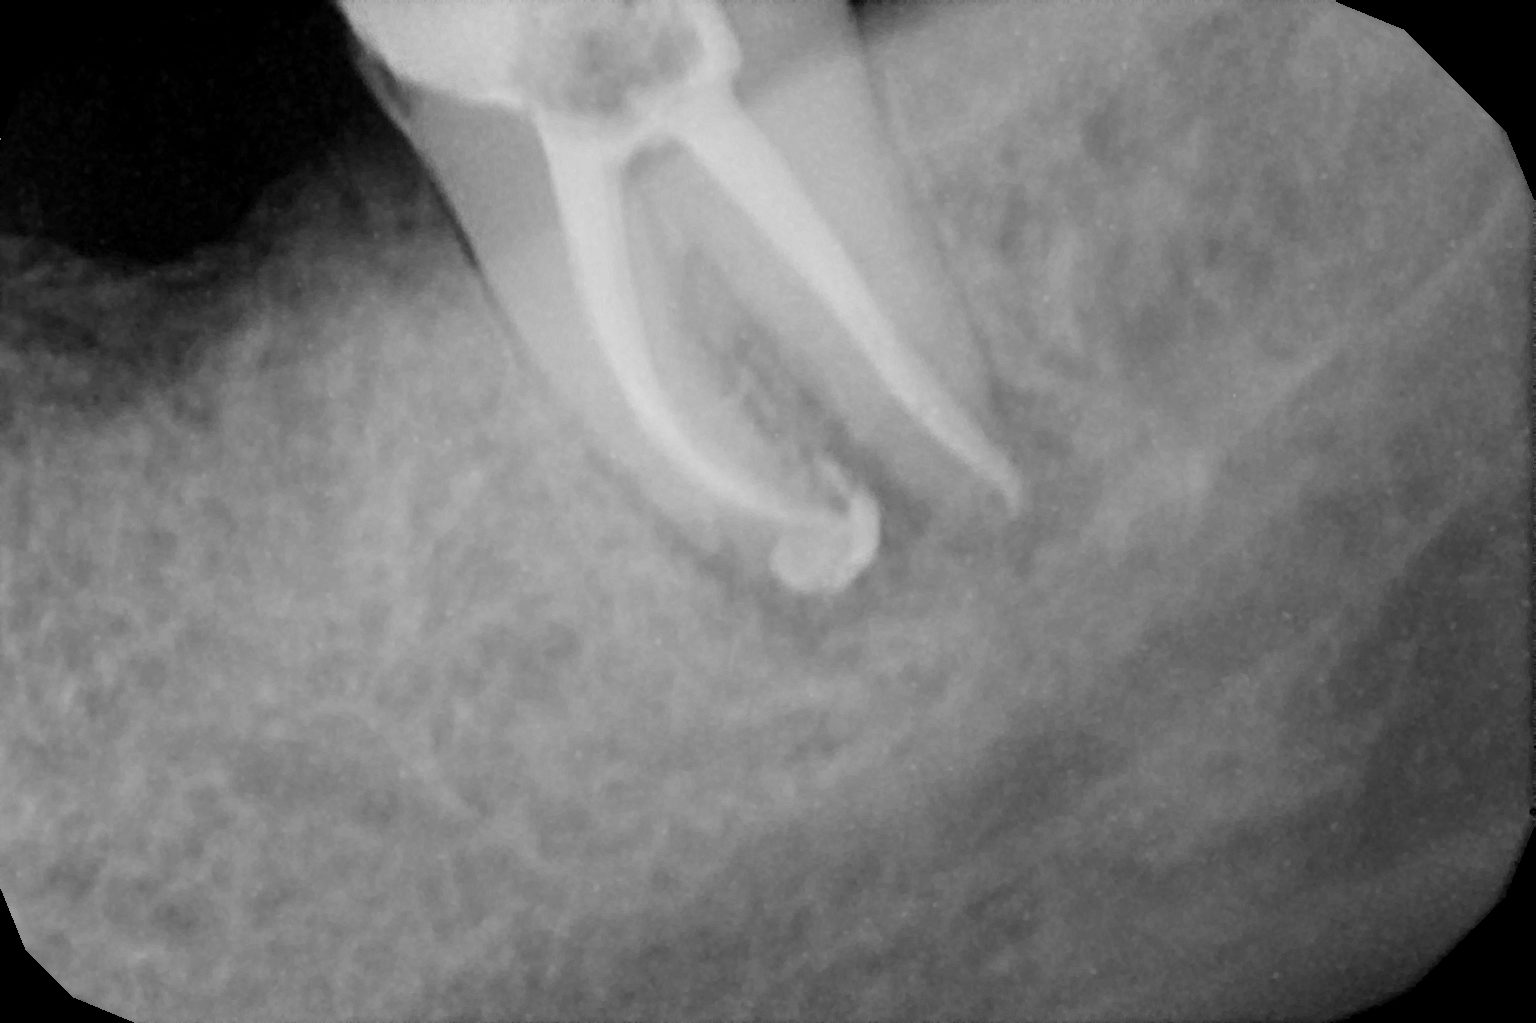

When the tooth is is sensitive to particularly hot and cold. When you cannot chew from that side or there is associated action of pain and swelling with same tooth, root canal treatment can save the tooth. For root canal treatment our clinic is equipped with state-of-the-art facility. We are following the protocol that is universally accepted and considered as a gold standard We are using rubber Dam for maximum possible cases. The root canal treatment is done under local anaesthesia that's why mostly it is painless . The rubber Dam isolation helps in proper irrigation and it provides much needed ease to the operating dental surgeon and the patient . The sealer and filling material are one of the Prime requisite of quality root canal treatment, it needs use of multiple X rays to really judge whether the results are acceptable or not. In older days root canal was just about cleaning the decade portion, removing the Pulp and filling it with biocompatible material but nowadays the root canal treatment it is very much advanced the precision is increased manifold. The materials and armamentarium that is required for efficient root canal have advanced in exclusion initial ways the the Abstract of all these things is the patients are getting great results after root canal treatment. Only the root canal is not sufficient to make a tooth functional again ,it needs use of Core buildup material and complete coverage Crowns according to the tooth position. During Covid19 time we have studied and implemented use of of high strength composites in our practice and the results of it are amazing many times it has saved tooth from being restored with crown. In some cases where the tooth is grossly carious we need a complete coverage crown. The materials and the Crown materials are are available in various price ranges. We prefer only the best of materials for our patients. We believe that to perform best treatment we need best of the armamentarium and best of the material for our patients who value and deserve the best of the treatment.